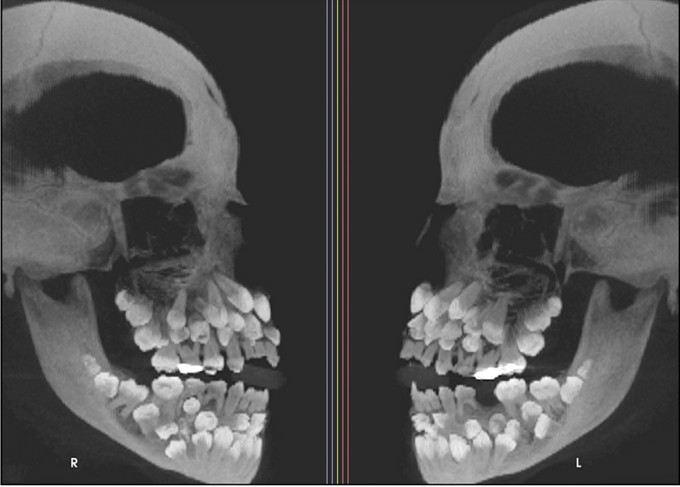

Đi nhổ răng sữa, một bé gái 11 tuổi đã khiến nha sĩ sốc nặng khi phát hiện phim chụp X-quang cho thấy cô bé có 81 chiếc răng trong miệng.

Các hãng thông tấn nước ngoài đã đưa tin về một trường hợp y khoa xảy ra ở Brazil, nơi một bé gái 11 tuổi đến gặp nha sĩ để nhổ răng sữa. Tuy nhiên, kết quả chụp X-quang cho thấy miệng bé có tổng cộng 81 chiếc răng, bao gồm 31 chiếc răng thừa. Trường hợp hiếm gặp này sau đó đã được đăng trên một tạp chí y khoa và trở thành chủ đề nóng hổi.

Cụ thể, bé gái 11 tuổi 8 tháng ở Minas Gerais, Brazil, đã đến một phòng khám nha khoa để kiểm tra răng miệng và dự định nhổ hàng răng sữa trên cùng vốn vẫn chưa rụng. Tuy nhiên, kết quả chụp X-quang cho thấy một phát hiện gây sốc, thực tế bé có 18 răng sữa, 32 răng vĩnh viễn và 31 răng thừa, tổng cộng là 81 răng.

Bé gái có 81 chiếc răng khiến nha sĩ bất ngờ.

Khi khám răng, bác sĩ nhận thấy chỉ có 5 răng vĩnh viễn đã mọc, trong khi vẫn còn khá nhiều răng sữa. Để đánh giá toàn diện hơn tình trạng răng miệng của bé, bác sĩ đã chỉ định chụp X-quang tổng quát và chụp sọ nghiêng.

Những hình ảnh cho thấy nhiều răng bị biến dạng và nằm sâu trong nướu, khiến việc phân biệt giữa răng bình thường và răng thừa rất khó khăn. Trung bình, một người trưởng thành có 32 chiếc răng và những chiếc răng thừa này được gọi là "siêu răng". Thông thường, chỉ có 1 hoặc 2 chiếc răng thừa.